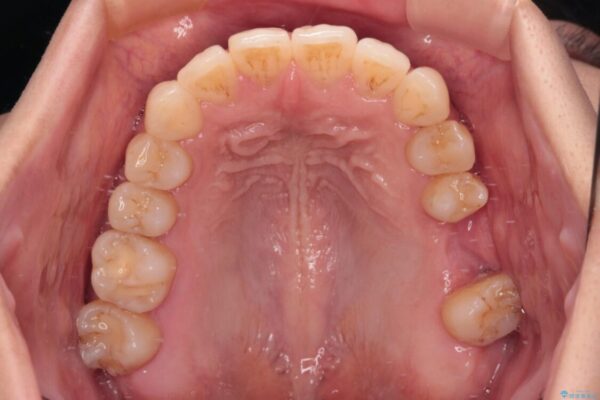

治療後

• インビザラインによる矯正治療と奥歯のインプラント治療 治療後画像